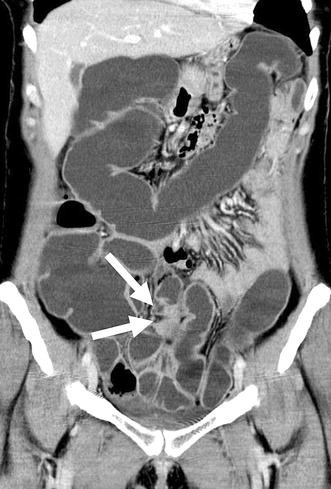

Экстрагенитальный эндометриоз- это форма эндометриоза, при которой очаги располагаются за пределами половых органов (матки, яичников, маточных труб). Его иногда называют «великим маскарадом», потому что симптомы могут маскироваться под другие болезни, что приводит к годам неправильных диагнозов.

-Эндометриоз лимфатических узлов. Обычно бессимптомный.

-Эндометриоз печени, селезенки, поджелудочной железы и даже конъюктивы глаза (который сопровождается, известными всем, кровавыми слезами)